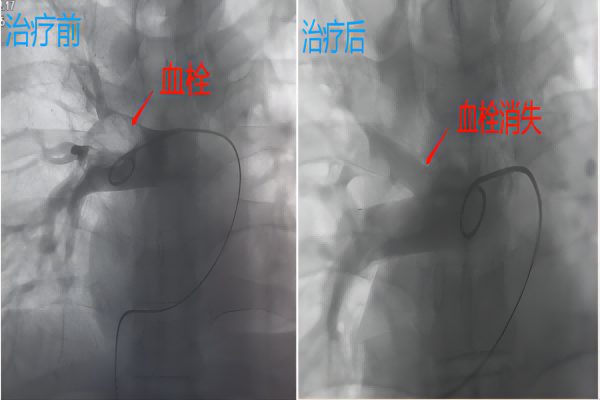

尹哲主任立即上报医务科,并在医务科主持下组织呼吸科等科室开展多学科会诊,考虑到患者的年龄、疾病特点,为了减少栓子再脱落、溶栓出血的风险,初步决定行介入导管下肺动脉溶栓术+下肢静脉滤器植入术。在做足做充分术前准备后,于12时患者被推进介入导管室手术,40多分钟后手术顺利完成安返病房,患者胸闷气短症状缓解,生命体征平稳。

该患者既有下腔静脉血栓又有肺栓塞,釆用下腔静脉滤器“堵”,介入导管“溶”的方法,看似矛盾,实则辩证施治,巧妙兼融。随着腔内技术的发展,导管接触溶栓已逐渐成为该病的重要治疗方法之一,该方法微创、有效、精准,最大限度地溶解血栓的同时又避免了全身溶栓出血并发症的风险,值得推广!但早期确诊、果敢施治为患者赢得宝贵治疗时机也至关重要!